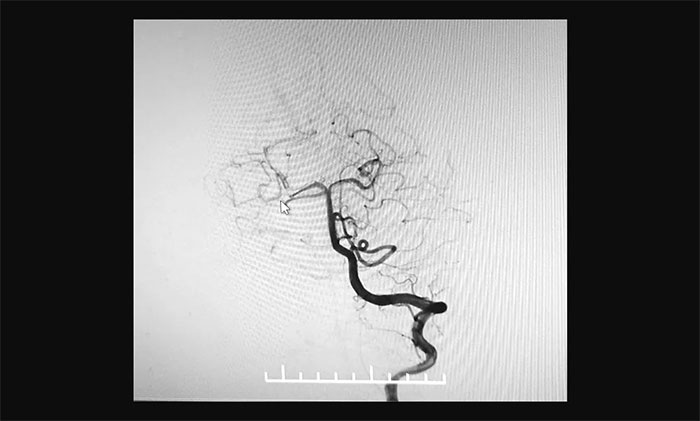

最终,在麻醉科团队及导管室介入团队的密切配合和监护下,神经外科于耀宇主任团队历时2小时,为王女士顺利实施脑血管造影+颅内动脉瘤栓塞术。术中,DSA造影确诊右侧小脑上动脉夹层动脉瘤,动脉瘤瘤体大小约为4x3 mm。术中,于耀宇主任凭借娴熟的技术,克服血管迂曲等困难,将栓塞导管成功送入夹层动脉瘤内,最终顺利栓塞夹层动脉瘤。术后,再次造影未见动脉瘤显影,见远端分支显影良好,“炸弹”危险被成功解除。术后,患者顺利苏醒,无神经功能障碍。

▲ 栓塞前

▲ 栓塞后